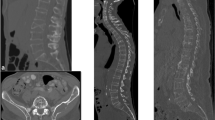

The study was done for the first 29 patients with MM (14 males, 15 females, age 67 ± 13 years, mean ± standard deviation) who were examined with WBLDMDCT protocol in our department, using the CT scanner 64 Brillance, Philips Medical System. The patients were positioned supine, with their arm over the head. A survey scan was performed to set the initial and end points of the diagnostic scan, with the parameters of acquisition and reconstruction shown in Table 1. The scan length was such that humera, head, neck, torso and femura were included, as shown in Fig. 1A-a.

A The survey image used to plan the scan (a), an axial image for each of the segments investigated, including head and humera (b), neck (c), chest (d), abdomen (e), pelvis (f), femura (g) and finally the dose report (h). B Some images of the Rando phantom used to simulate the conventional examination of the skeleton: (i) anterior–posterior skull, (l) lateral skull; (m) pelvis; (n) ribs; (o) anterior–posterior dorsal and lumbar spine; (p) lateral spine

The CTDIvol for the protocol in use was equal to 2.62 mGy at 120 kV and 3.88 at 140 kV. Only two large male subjects were studied at 140 kV. The dose indexes, shown in the dose report, are related to the cylindrical phantom of 32 cm of diameter. An example of the dose report is shown in Fig. 1A-h. The contributions to the patient dose due to both survey and diagnostic scan have been considered.